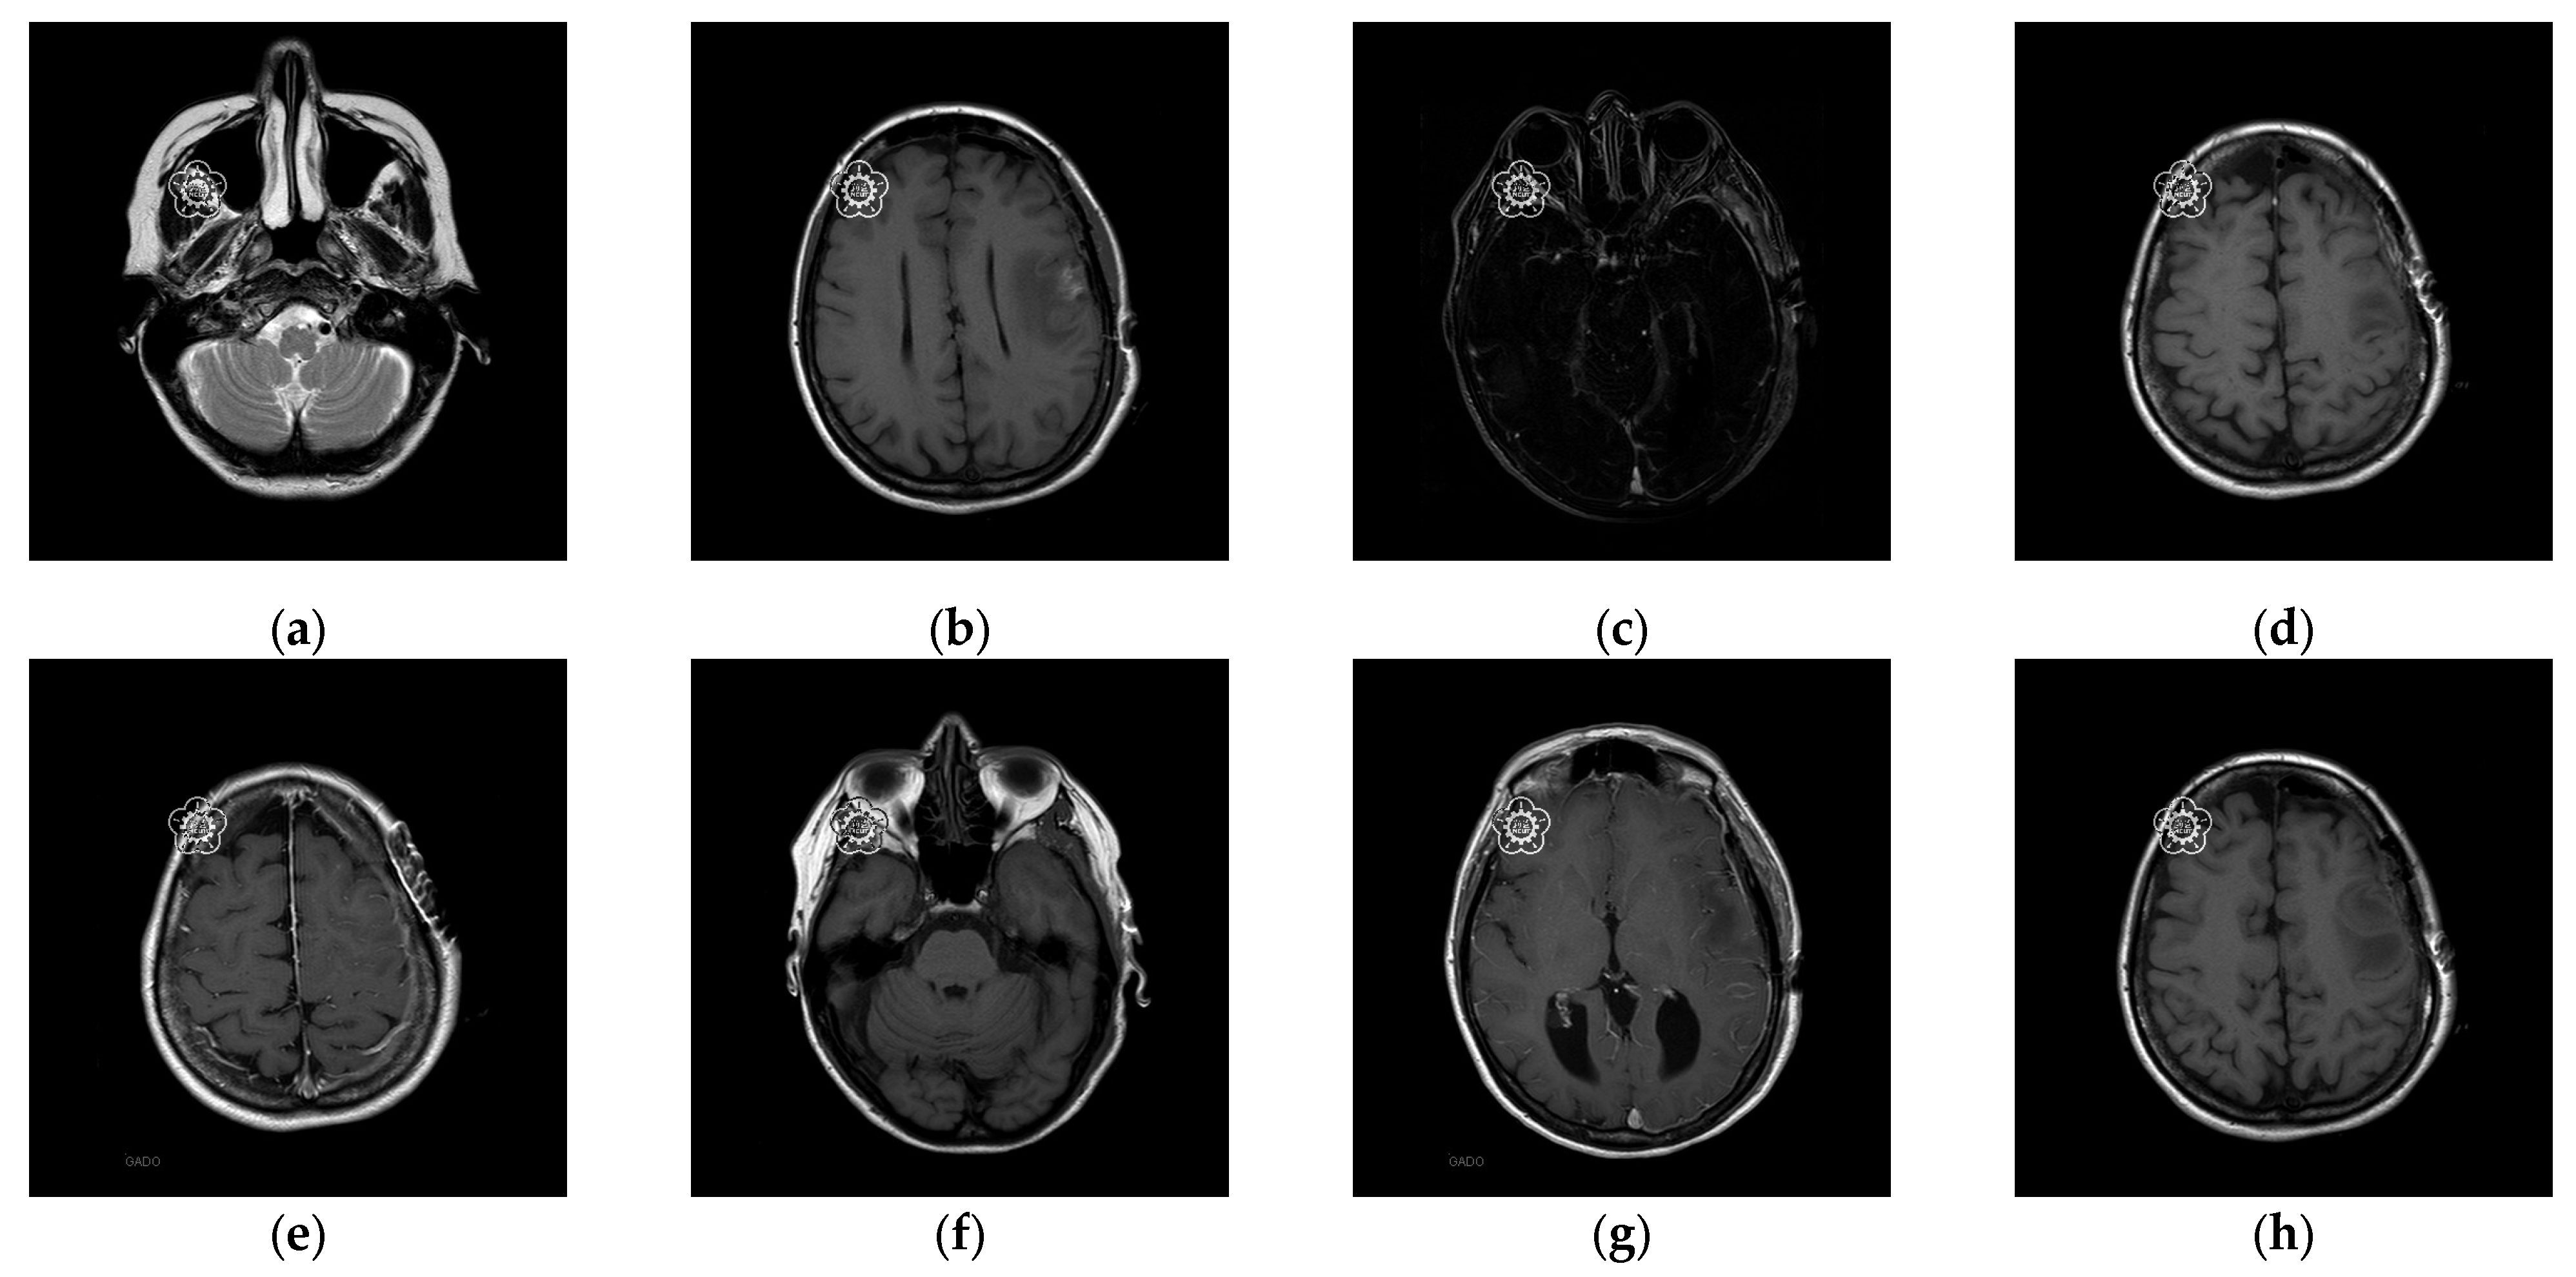

To better align our VUF-MIWS with the practical needs of clinicians for authenticating medical image sources, we conducted a pilot interview at a regional hospital. In this interview, we defined the critical diagnostic reference area of a medical image as the ROI (Region of Interest) and divided it into nine sub-regions, as shown in Figure 14. We then asked seven doctors to indicate their two most preferred locations for visible watermarks. Based on the collected feedback, sub-region A received the highest number of votes (a total of nine), followed by sub-regions E and I (both receiving five votes). Therefore, sub-region A was selected as the watermark position for the first and second experiments. The resulting watermarked images for the first experiments are displayed in Figure 15.

Figure 15.

Eight watermarked images. (a) Watermarked 10.png; (b) Watermarked 11.png; (c) Watermarked 14.png; (d) Watermarked 16.png; (e) Watermarked 19.png; (f) Watermarked 26.png; (g) Watermarked 31.png; (h) Watermarked 57.png.